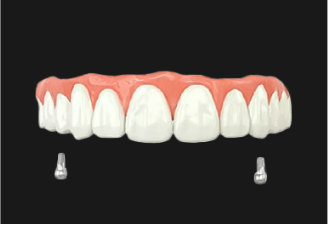

기존 틀니의 단점인 저작 시에 유발되는 잇몸 통증과

자주 탈락되는 장치의 불편함을 보완하고, 임플란트의 기능성을

결합하여 잃어버린 치아기능을 회복시켜주는 치료방법입니다.

구강내 식립된 임플란트가

틀니를 잡아주는 역할을 하여,

자연치아의 70~80% 정도의

저작력을 발휘합니다.

완전 틀니를 할 경우

잇몸뼈 손실이 발생할 가능성이 높지만

임플란트 틀니는 손실 가능성을

최소화 할 수 있습니다.

입천장을 덮는 완전 틀니에 비해

이물감이 적어 일상생활에서도 음식을

섭취하는데 편안함을 느낄 수 있습니다.

1단계 치아상태에 따른 2~6개 정도의 임플란트 식립

2단계 임플란트와 틀니를 연결하는 장치 부착

3단계 제작된 틀니 연결장치에 장착하여 고정